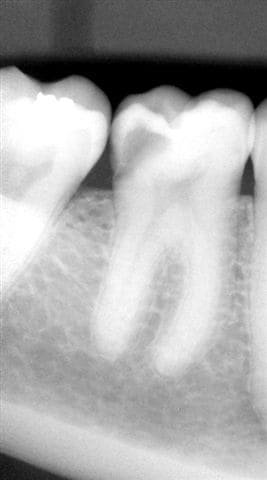

du bureau nous passons au fauteuil, où, dès qu'elle est installée je lui propose de faire une radio, elle me répond que c'est très dangereux pour son foetus, je la rassure, installe un tablier de protection et voilà ce que je découvre sur la retro alvéolaire...

Des photos ont également été faites avec ma caméra endo-buccale, les voici...